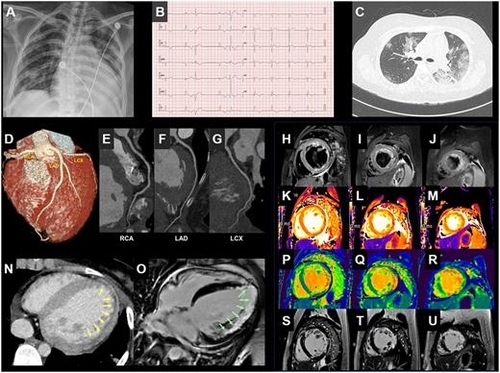

이에 의료진은 심근염을 의심하고 컴퓨터단층촬영(CT)과 자기공명영상(MRI) 검사를 추가로 시행했다. 그 결과, 심장이 정상보다 비대해지고, 심장 조직에 손상도 있는 것으로 확인됐다. 다만, 관상동맥이 막히지 않은 점으로 미뤄 심근경색은 아니라고 의료진은 판단했다.

김 교수는 "국내에서 코로나19 환자의 심장질환 사례가 정식으로 보고된 건 이번이 처음"이라며 "이 환자의 경우 입원 후 심장 박출률이 25%가량 떨어지는 상태에서 (의료진이) 심근염을 의심하고 CT, MRI 등 추가 검사로 확진해 치료했지만, 이런 의심이 없었다면 심근염 치료가 늦어졌을 수도 있다"고 말했다.